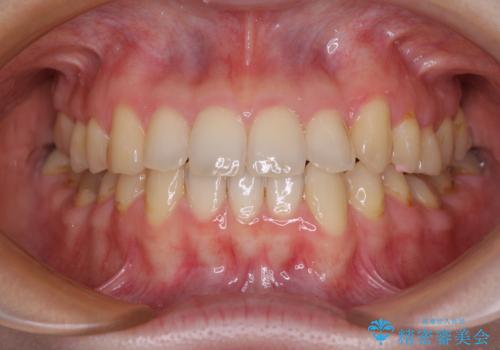

前歯のデコボコを治したい 高校生のインビザライン治療

担当医 藤巻太一朗